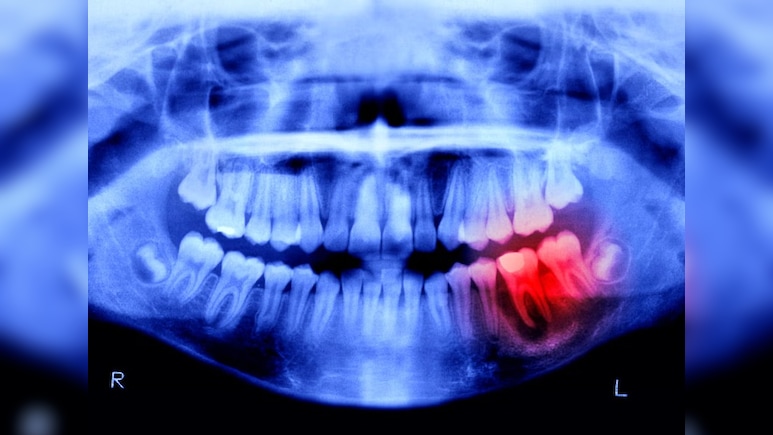

Tooth Regeneration Human Trial: इंसानी शरीर में 206 हड्डियां होती हैं, जो टूटने पर खुद को ठीक करने की ताकत रखती हैं, लेकिन दांत ऐसे नहीं होते. दांत एक बार गिर जाएं या खराब हो जाएं, तो वे खुद से दोबारा नहीं उगते. यही वजह है कि दुनिया भर में लाखों लोग tooth loss या edentulism की समस्या से जूझ रहे हैं, लेकिन अब यह तस्वीर बदल सकती है. popularmechanics.com के मुताबिक, जापान के वैज्ञानिक एक ऐसी tooth regrowth medicine को इंसानों पर आजमा रहे हैं, जो भविष्य में दांतों के इलाज की दुनिया बदल सकती है.

ओसाका के Kitano Hospital के डेंटल रिसर्च हेड डॉ. कात्सु ताकाहाशी के नेतृत्व में यह ट्रायल सितंबर 2024 से शुरू हुआ है. इस 11 महीने के ट्रायल में 30 से 64 साल के 30 पुरुष शामिल हैं, जिनका कम से कम एक दांत गायब है. दवा को नसों के जरिए दिया जा रहा है, ताकि उसकी सुरक्षा और असर दोनों की जांच हो सके.

यह रिसर्च USAG-1 नाम के एक एंटीबॉडी पर आधारित है, जो दांतों की ग्रोथ को रोकता है. क्योटो यूनिवर्सिटी के वैज्ञानिकों ने एक खास monoclonal antibody विकसित की, जो USAG-1 और BMP (Bone Morphogenetic Protein) के बीच की रुकावट को खत्म कर देती है. जानवरों पर हुए परीक्षणों में दांत दोबारा उगते देखे गए थे.

अगर यह ट्रायल सफल रहता है, तो अगला चरण 2 से 7 साल के उन बच्चों पर होगा, जिनके जन्म से ही चार या उससे ज्यादा दांत नहीं हैं. वैज्ञानिकों का लक्ष्य है कि 2030 तक tooth regrowth treatment आम लोगों के लिए उपलब्ध हो सके. अगर यह दवा सफल होती है, तो यह डेंटल साइंस की सबसे बड़ी क्रांति होगी. दांतों की कमी सिर्फ सौंदर्य नहीं, बल्कि सेहत से जुड़ा बड़ा मुद्दा है और यह खोज लाखों लोगों की जिंदगी बदल सकती है.